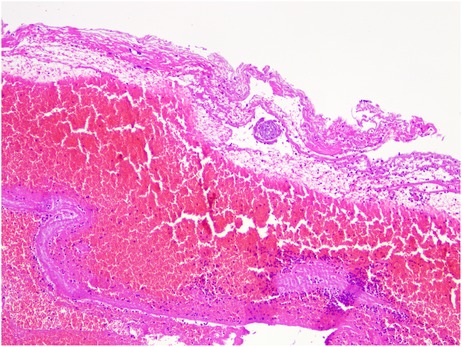

Postoperatively, the patient's right upper abdominal pain (Kehr's sign) was relieved, and the patient's blood β-hCG value was 402.5 mIU/mL on the 2nd postoperative day. Postoperative pathology results confirmed the presence of pregnancy chorionic tissue (Figure 3). The patient tolerated chemotherapy and two surgeries well and the postoperative incision healed satisfactorily. The patient recovered well after surgery and was discharged 5 days after surgery. No adverse events or complications occurred during treatment or follow-up, the patient expressed high satisfaction with the treatment process and nursing care. The postoperative β-hCG level gradually decreased to within the normal range, indicating that the pregnant tissue had been completely removed (Figure 4).

Figure 3. Pathological microscopy showing hemorrhagic exudate and degenerated villous tissue (HE stain, × 100).